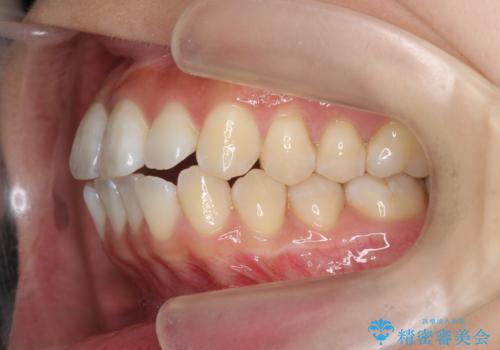

- 前歯の噛み合わせの開きの改善を求めて来院されました。

奥歯はほとんど動かさず(奥歯の噛み合わせはほとんど変えず)前歯のIPR矯正でガタつき前突感(出っ歯感)の改善を計画します。

ほとんど前歯のみの矯正治療であることからトータル14枚のマウスピースで並べるインビザラインライトによる治療を行います。

インビザラインライトは全14枚のマウスピースで行う軽度なガタつきなどの改善を目的とする矯正治療です。(約3.5ヶ月)

今回の治療では追加でマウスピース治療を行なったため、半年弱の治療期間となりました。